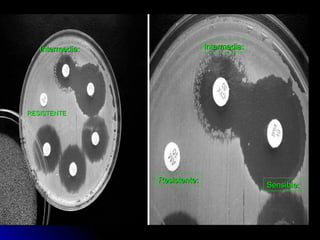

Interpretación: En éste método la interpretación de los

resultados está basado sobre la relación entre la

concentración inhibitoria mínima (MCI) y el diámetro de

la zona de inhibición

El sistema más simple comprende solamente dos

categorías susceptibles y resistentes, ésta clasificación

aunque ofrece muchas ventajas para los propósitos

estadísticos epidemiológicos es demasiado inflexible

para la utilización del clínico.

En el método de Kirby Bauer modificado se reconocen

tres categorías de susceptibilidad que son sensible,

resistente e intermedio

 Sensible.-Sensible.- Un microorganismo es llamado sensible a unUn microorganismo es llamado sensible a un

antimicrobiano cuando la infección causada por él es probable queantimicrobiano cuando la infección causada por él es probable que

responda favorablemente al tratamiento con éste agente a las dosisresponda favorablemente al tratamiento con éste agente a las dosis

usuales recomendadas.usuales recomendadas.

 Intermedia.-Intermedia.- Cuando la infección es probable que respondaCuando la infección es probable que responda

favorablemente el tratamiento a dosis inusualmente altas delfavorablemente el tratamiento a dosis inusualmente altas del

antimicrobiano.antimicrobiano.

 Resistente.-Resistente.- Es término que implica la expectativa de que elEs término que implica la expectativa de que el

microorganismo no responda a una droga dada, independientementemicroorganismo no responda a una droga dada, independientemente

de la dosis y localización de la infección.de la dosis y localización de la infección.

Resistente:Resistente:

Sensible:Sensible:

Intermedia:Intermedia:Intermedia:Intermedia:

RESISTENTERESISTENTE